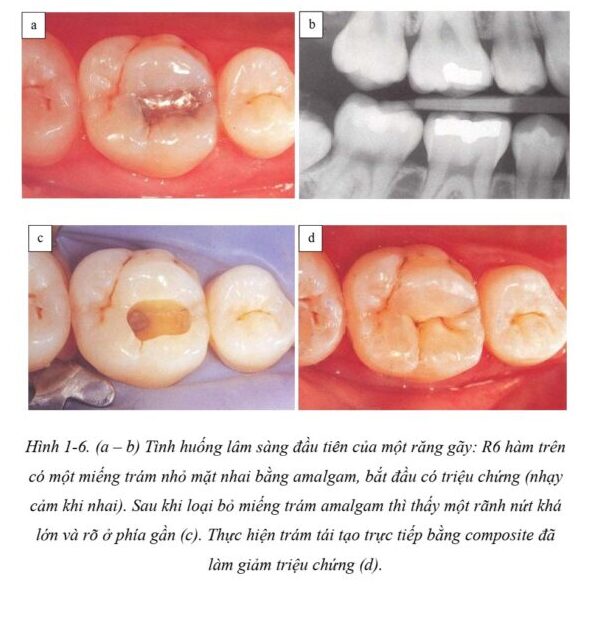

Hiện nay vẫn không có một loại vật liệu kim loại truyền thống nào đáp ứng một cách thỏa đáng những yêu cầu nói trên. Với amalgam, nứt gãy răng, đổi màu răng đã và vẫn đang là những trở ngại thường gặp (H1-5 đến H1-8).